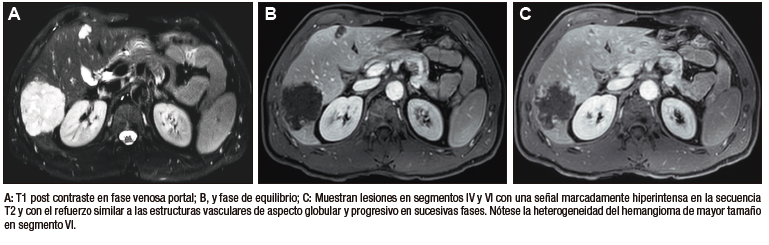

En la TC los hemangiomas son lesiones de bordes netos y frecuentemente de contornos lobulados. Al estar compuestas por vasos, su densidad es igual a la del pool sanguíneo, tanto en las imágenes sin contraste como en las diferentes fases de la evaluación poscontraste. El refuerzo es típicamente globular y progresivo, de forma centrípeta. (Figura 1) En los hemangiomas de mayor tamaño el pasaje del contraste al centro de la lesión toma más tiempo e incluso no ocurre en aquellos más voluminosos.

Figura 1. Hemangioma en tomografía computada. Imágenes axiales de la TC sin

contraste